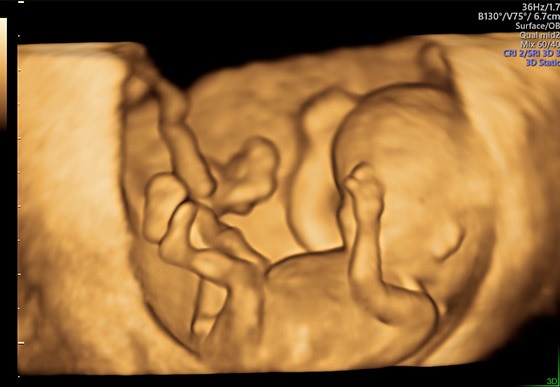

Простота получения 3D-изображений

Визуализация в режимах 3D/4D позволяет исследовать дополнительные анатомические плоскости, повышая вашу уверенность в диагностике.

- Визуализация плоскостей недоступных для исследования при 2D-сканировании, для более точной диагностики.

- Высокая производительность, благодаря возможности анализировать 3D данные как во время, так и после завершения исследования.

- Просмотр и обработка объемных изображений в разных плоскостях или с использованием разных режимов сканирования.

- Точная постановка диагноза благодаря экспертным 3D/4D-технологиям Voluson.

3D-технологии Voluson позволяют получить дополнительные плоскости визуализации, недоступные при рутинном сканировании в 2D.

- Быстрое получение 3D/4D-изображений благодаря технологии SonoRenderlive — автоматического определения плоскости визуализации объемных изображений 3D/4D.